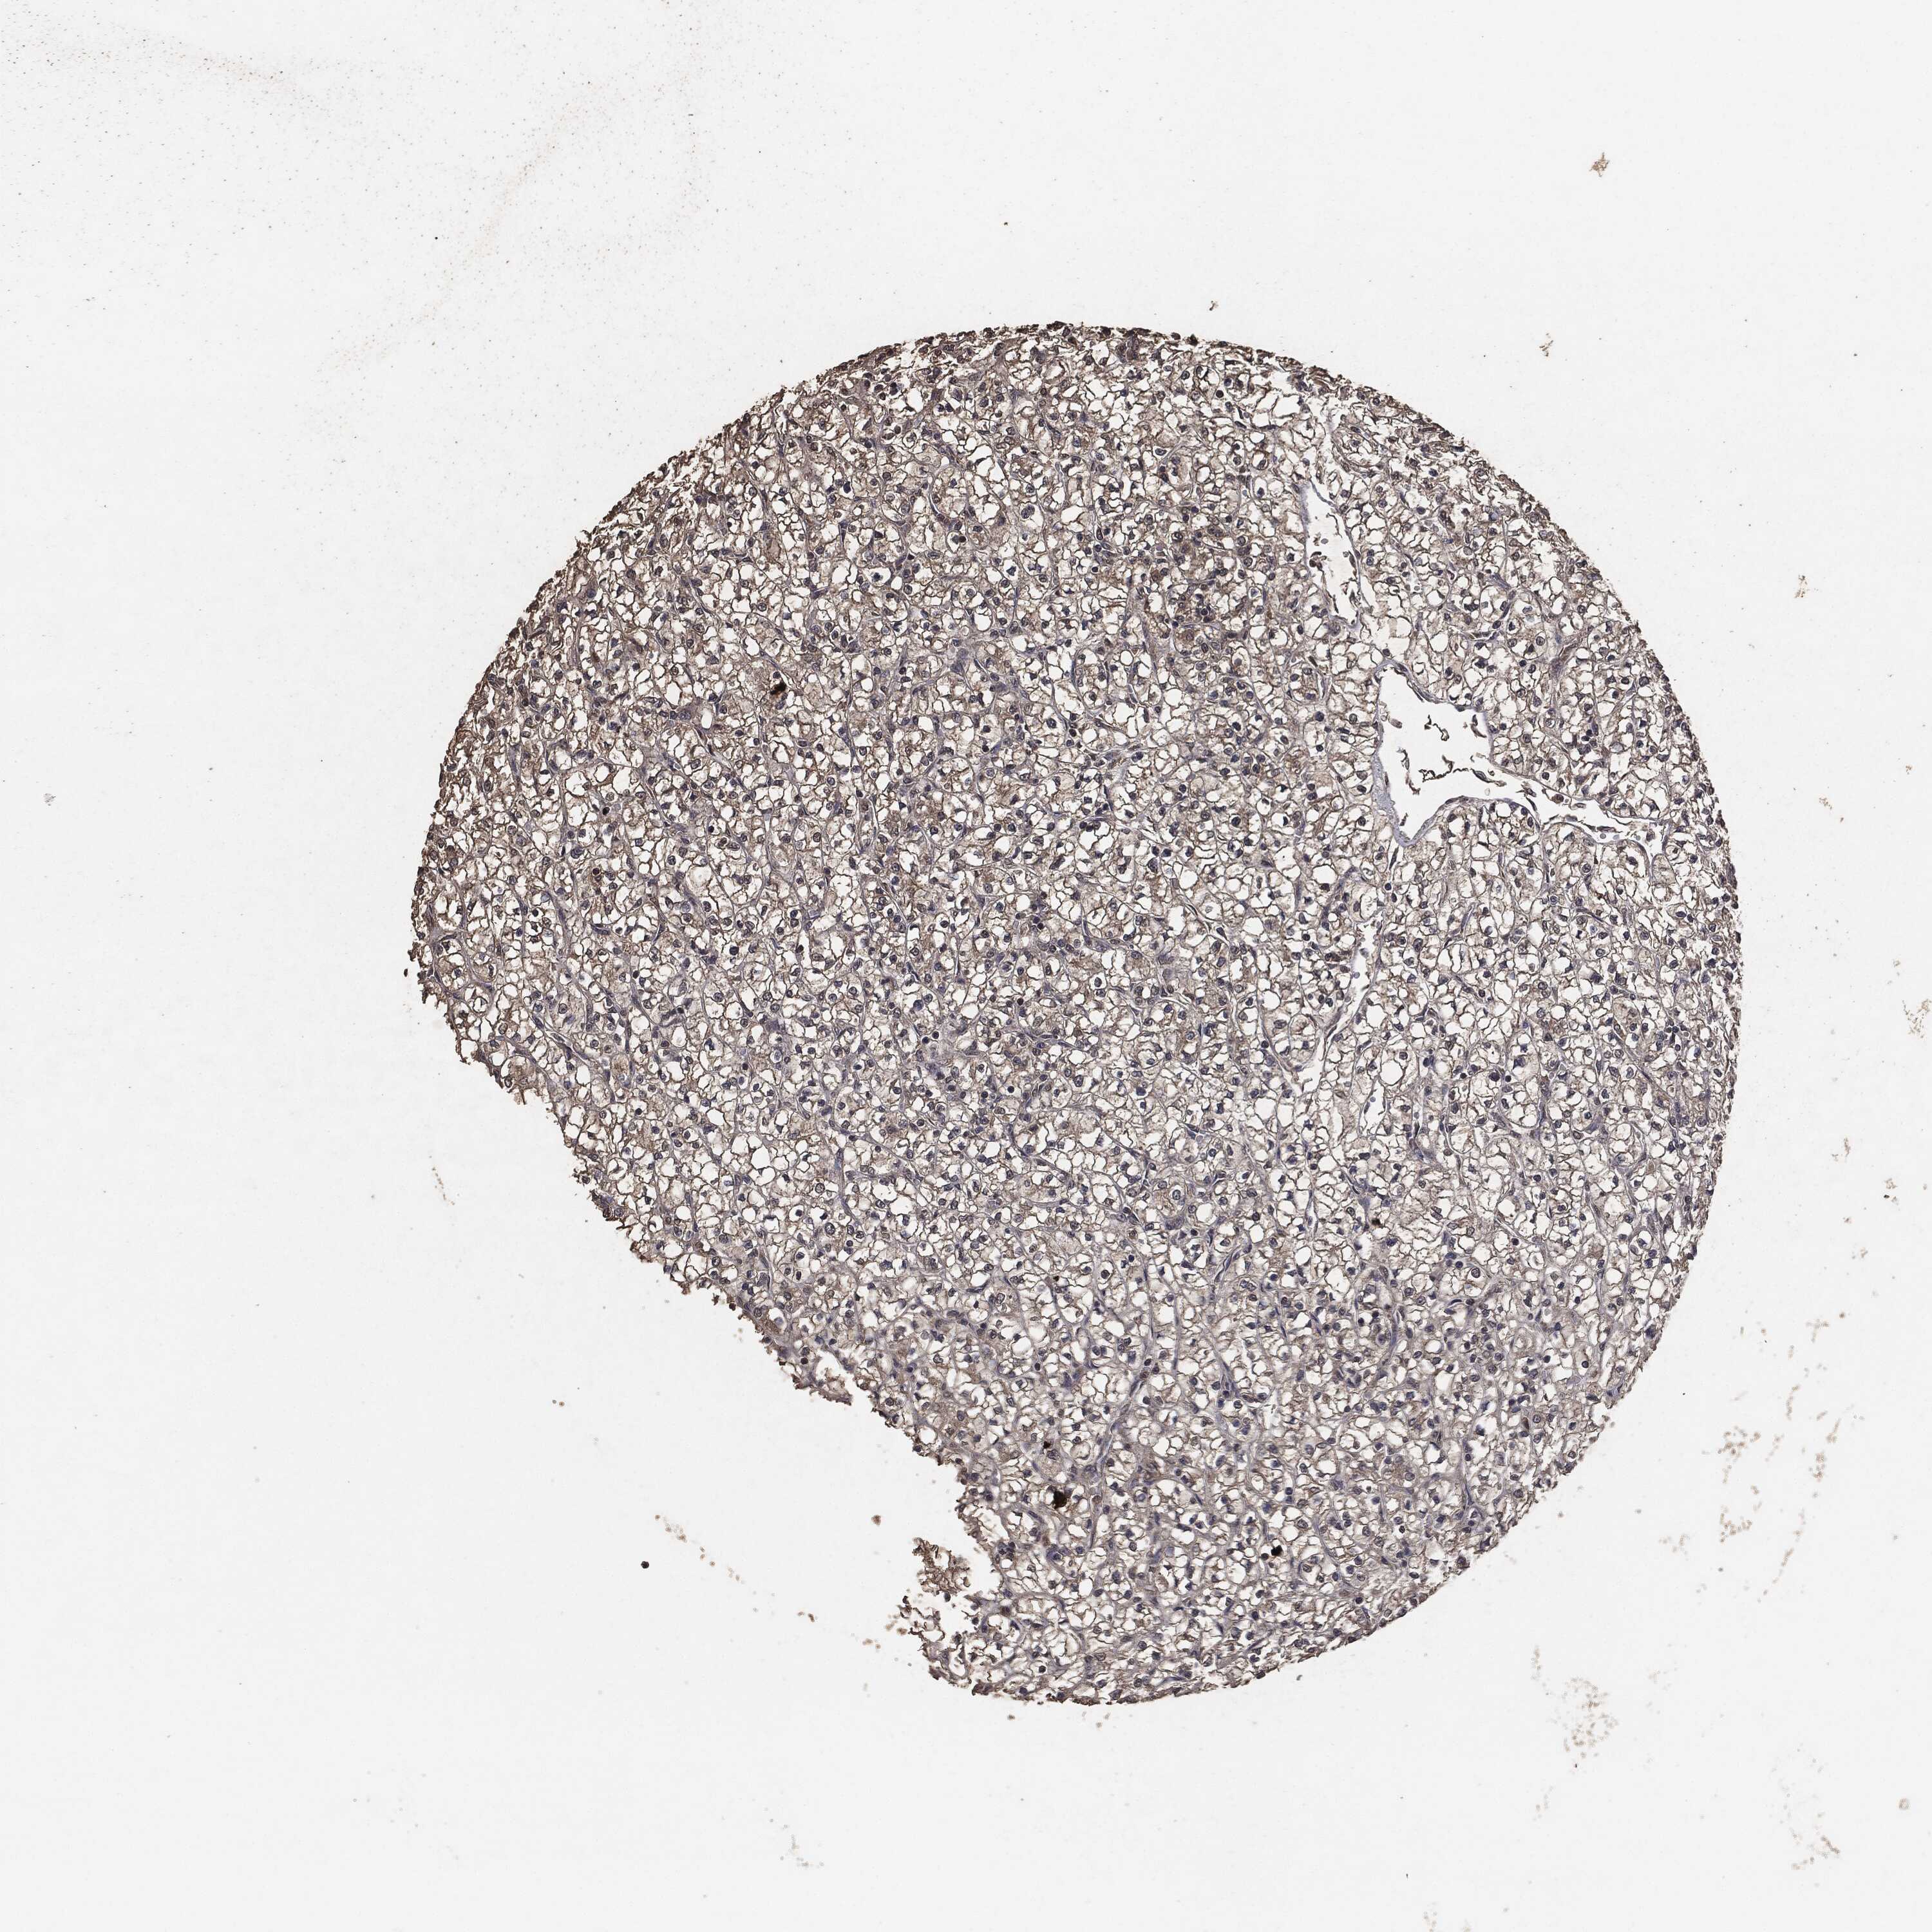

KIDNEY RENAL CLEAR CELL CARCINOMA (TCGA) - Interactive survival scatter ploti

The Survival Scatter plot shows the clinical status (i.e. dead or alive) for all individuals in the patient cohort, based on the same data that underlies the corresponding Kaplan-Meier plots. Patients that are alive at last time for follow-up are shown in blue and patients who have died during the study are shown in red.

The x-axis shows the expression levels (FPKM) of the investigated gene in the tumor tissue at the time of diagnosis. The y-axis shows the follow-up time after diagnosis (years). Both axes are complimented with kernel density curves demonstrating the data density over the axes. The top density plot shows the expression levels (FPKM) distribution among dead (red) and alive patients (blue). The right density plot shows the data density of the survived years of dead patients with high and low expression levels respectively, stratified using the cutoff indicated by the vertical dashed line through the Survival Scatter plot. This cutoff is automatically defined based on the FPKM cutoff that minimizes the p-score. The cutoff can be changed by dragging the vertical line or by entering a cutoff value in the square labeled "Current cut-off".

Under the Survival Scatter plot the p-score landscape (black curve; left axis) is shown together with dead median separation (red curve; right axis). Dead median separation is the difference in median mRNA expression between patients who have died with high and low expression, respectively. It is calculated as follows: median FPKM expression of dead patients with high expression - median FPKM expression of dead patients with low expression. This is intended to aid the user in visually exploring custom cutoffs and the associated p-scores and dead median separation.

Individual patient data is displayed and can be filtered by clicking on one or more of the category buttons on the top of the page. Categories describing expression level and patient information include: high, low, alive, dead, female, male and tumor stages. The scale of the x-axis can be toggled between linear and log-scale by clicking on the "x log" button. Mouse-over function shows TCGA ID, patient information and mRNA expression (FPKM) for each patient.

& Survival analysisi

Kaplan-Meier plots summarize results from analysis of correlation between mRNA expression level and patient survival. Patients were divided based on level of expression into one of the two groups "low" (under cut off) or "high" (over cut off). X-axis shows time for survival (years) and y-axis shows the probability of survival, where 1.0 corresponds to 100 percent.

AKT1S1 is not prognostic in Kidney Renal Clear Cell Carcinoma (TCGA)

Best expression cut offi

Based on the FPKM value of each gene, patients were classified into two groups and association between prognosis (survival) and gene expression (FPKM) was examined. The best expression cut-off refers the FPKM value that yields maximal difference with regard to survival between the two groups at the lowest log-rank P-value. Best expression cut-off was selected based on survival analysis .

When clicking on this number, the vertical dashed line indicating cut-off, the interactive survival plot, and the Kaplan-Meier curve will be adjusted to show results based on the best expression cut-off.

: 41.02

P scorei

Log-rank P value for Kaplan-Meier plot showing results from analysis of correlation between mRNA expression level and patient survival.

N/A

TCGA RNA samplesi

RNA-seq data is reported as average FPKM (number Fragments Per Kilobase of exon per Million reads), generated by the The Cancer Genome Atlas (TCGA) .

Normal distribution across the dataset is visualized with box plots, shown as median and 25th and 75th percentiles. Points are displayed as outliers if they are above or below 1.5 times the interquartile range. FPKM values of the individual samples are presented next to the box plot.

Average pTPM 38.3

Number of samples 521